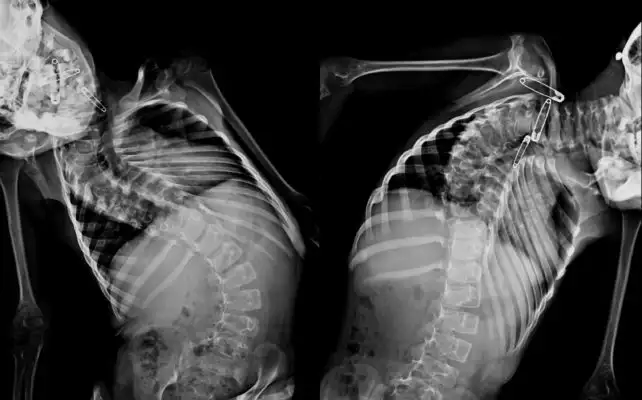

The procedures were quite complex, with each case requiring two surgeons working six to 10 hours in the operating room. “The local spine surgeons can do very good work, but only up to a certain limit. These were children they could not help because of the complexity of the deformities and the potential costs involved,” Parikh says.

Children with deformities this extreme require surgery or they risk becoming paralyzed before reaching early adulthood because the curvature of their spines can damage their spinal cords. The metal rods and implants they received will remain in their bodies for the rest of their lives.

The children who received treatment ranged from age 3 to 14. To take on these cases, the local hospital created a temporary pediatric intensive care unit staffed by local pediatricians 24-hours-a-day to provide post-op care. Local spine surgeons will perform follow-up procedures on the youngest patients to lengthen the spine implant rods as the children grow.